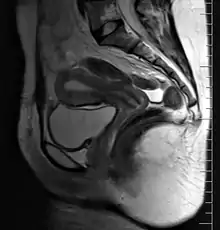

| Female reproductive system (human) | |

9. Vagina: 10. Hymen; 11. Lumen; 12. Wall; 13. Fornix (lateral)

14. Uterus: Parts: 15. Cervix; 16. Body and 17. Fundus. 18. Orifices: External and Internal; 19. Cervical canal; 20. Uterine cavity; Layers: 21. Endometrium; 22. Myometrium and 23. Perimetrium

24. Fallopian tube: 25. Isthmus; 26. Ampulla; 27. Infundibulum; 28. Fimbria (with 29. Fimbria ovarica)

30. Ovary

31. Visceral pelvic peritoneum: 32. Broad ligament (with 33. Mesosalpinx; 34. Mesovarium and 35. Mesometrium)

Ligaments: 36. Round; 37. Ovarian; 38. Suspensory of ovary

Blood vessels: 39. Ovarian artery and vein; 40. Uterine artery and veins; 41. Vaginal artery and veins

Other: 42. Ureter; 43. Pelvic floor (Levator ani); 44. Femoral head; 45. Hip bone; 46. Internal iliac vessels (anterior branches); 47. External iliac vessels; 48. Abdominal cavity